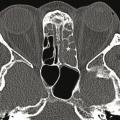

Image

Gonarthrose

GENOU

GONALGIE